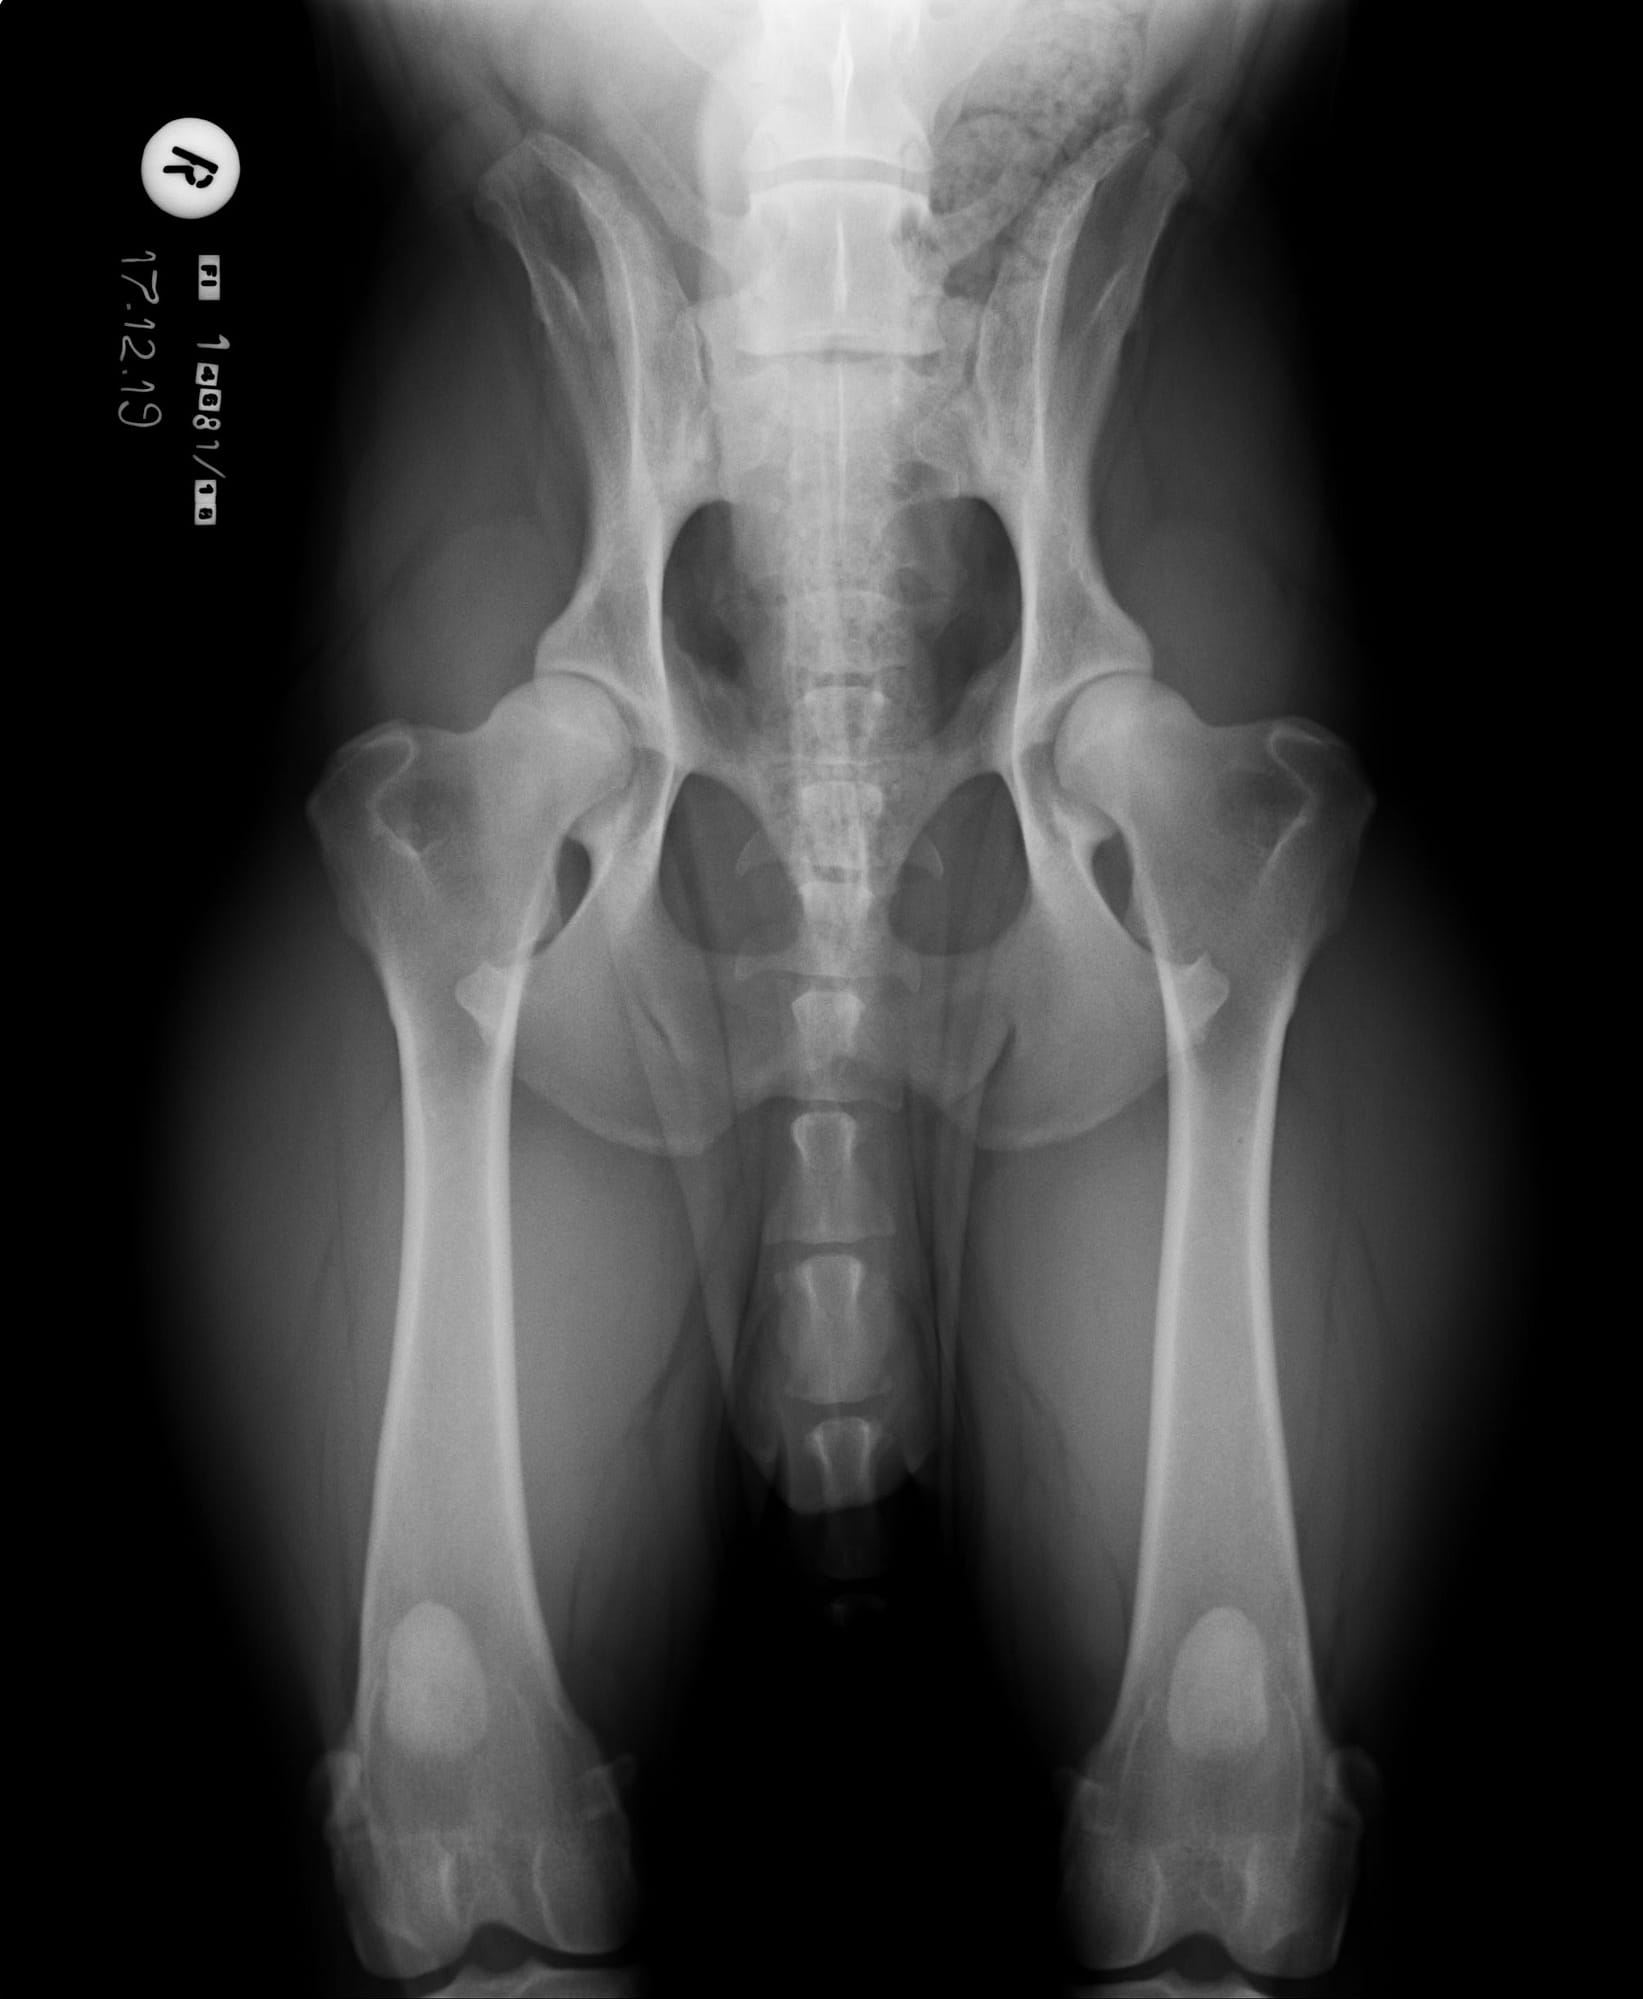

LTV3, epäsymmetrinen lanne-ristinikama näyttää olevan muita muotoja harmillisempi. Joissain tapauksissa epäsymmetriseen lanne-ristinikamaan liittyy vino lantio, joka saattaa aiheuttaa myös lonkkien epätasaista kehitystä. Tämä on varsin loogista; kun lantio on vino kohdistuu paine lonkkamaljoille epätasaisesti. Pidemmän ajan kuluessa epätasapaino voi kuluttaa toista lonkkamaljaa nopeammin ja aiheuttaa tätä kautta nivelrikkoa.

KoiraNetin mukaan 38,9% LTV3-lausunnon saaneista rhodesiankoirista on saanut lonkkien osalta lausunnon, jossa toinen lonkka on 1-2 astetta toista huonompi, esimerkiksi A/C (lokakuu 2020). Tutkimustulos LTV3 ei kerro koiran lantion asentoa.

”Asymmetrical LTV favours pelvic rotation over its long axis, resulting in inadequate femoral head coverage by the acetabulum on one side. Inadequate coverage of the femoral head favours subluxation, malformation of the hip joint, and secondary osteoarthritis. Asymmetrical hip conformation may therefore be the sequela of a LTV and mask or aggravate genetically induced canine hip dysplasia.”

(Flückiger M., Frank Steffen F. et al 2017)